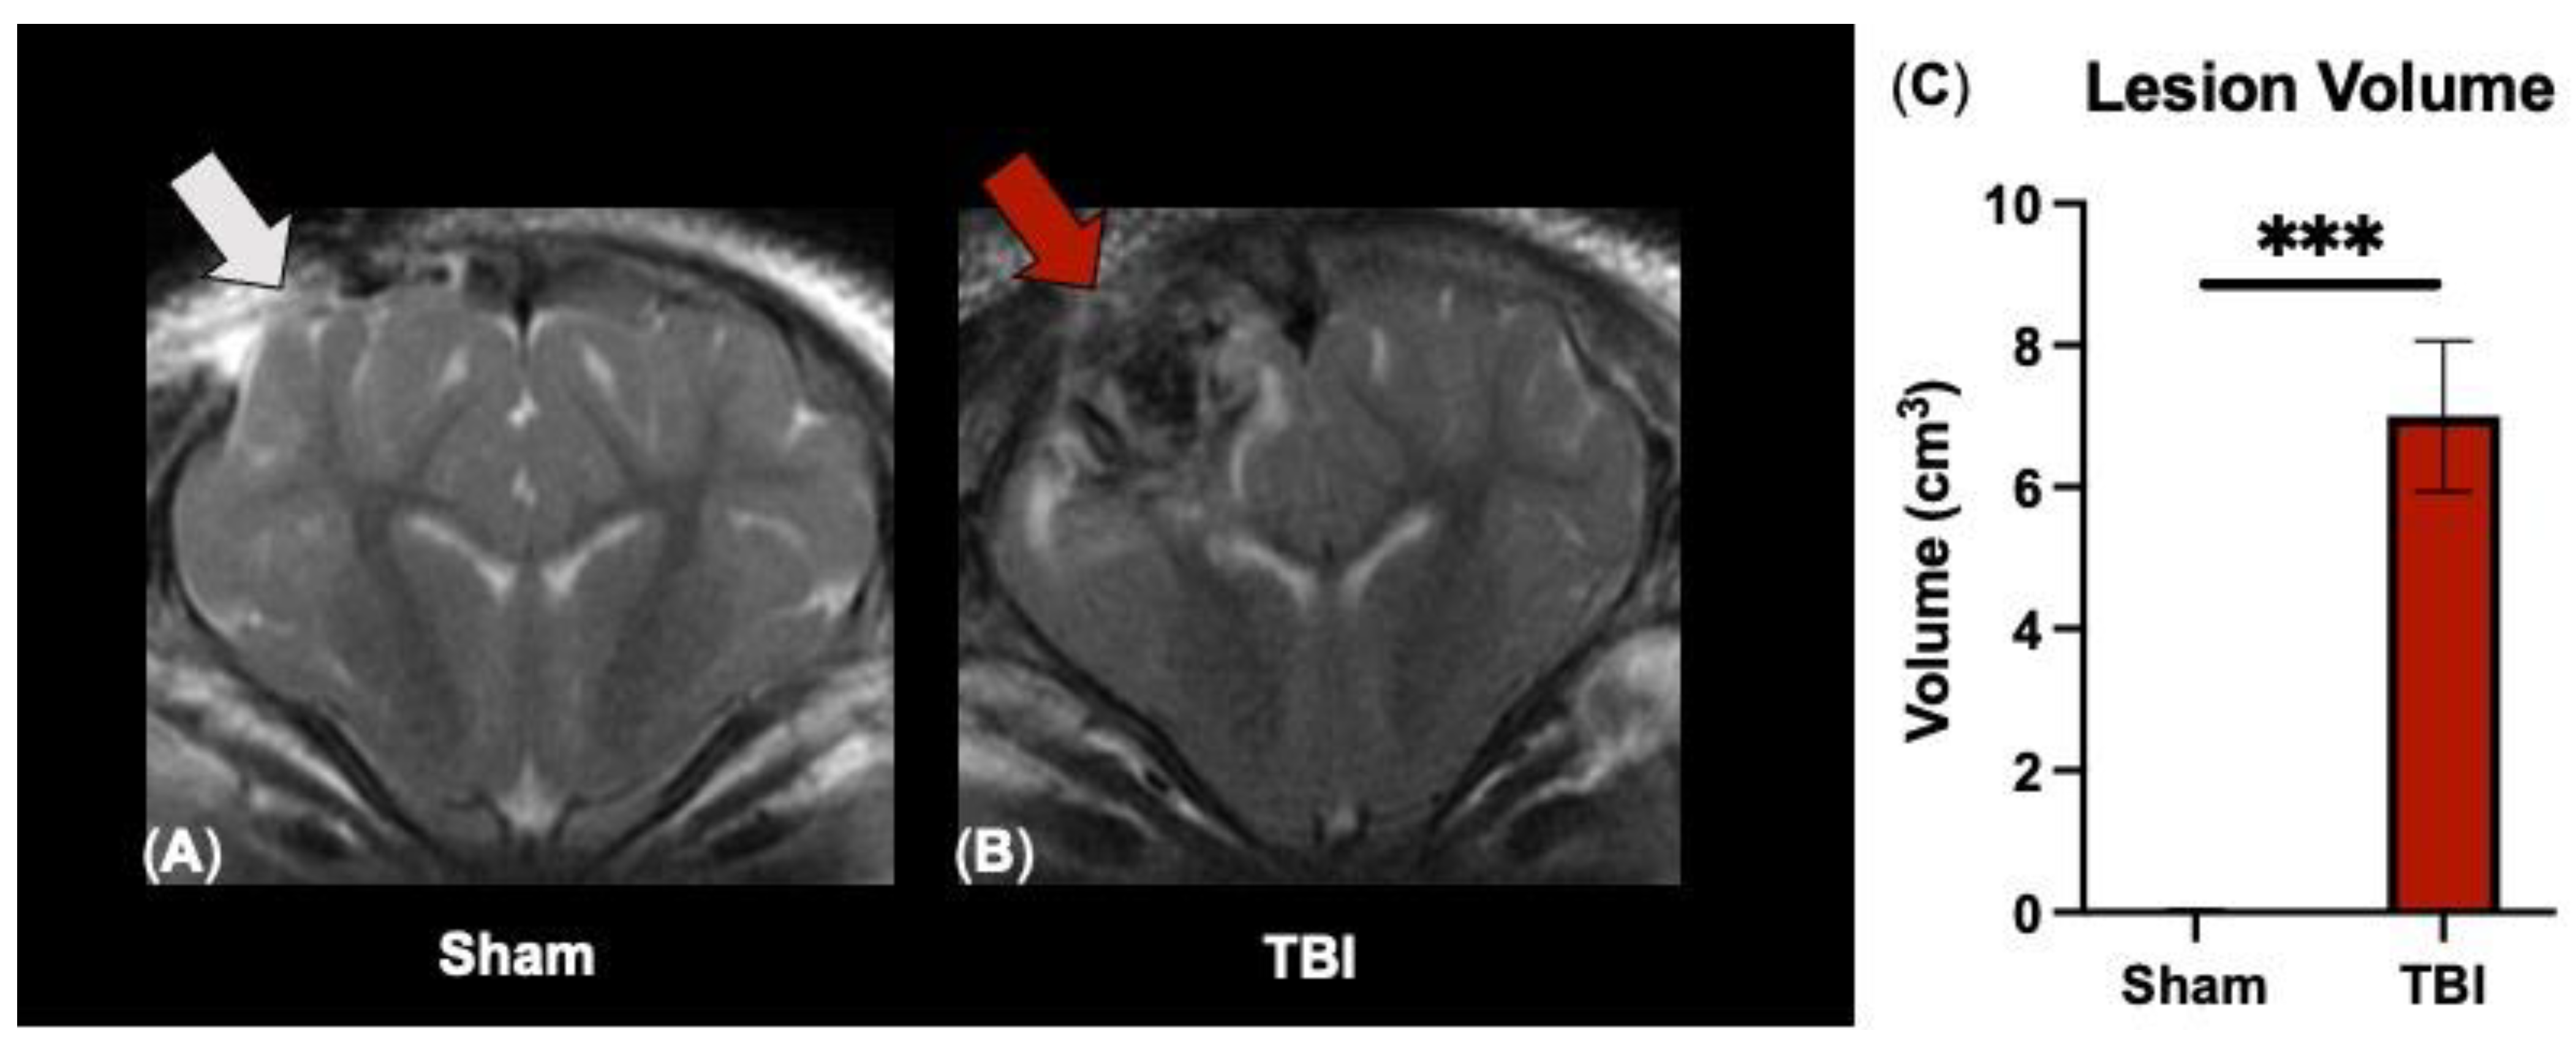

3.1. T2W Sequences Detect Significant Ipsilateral Lesioning following TBI